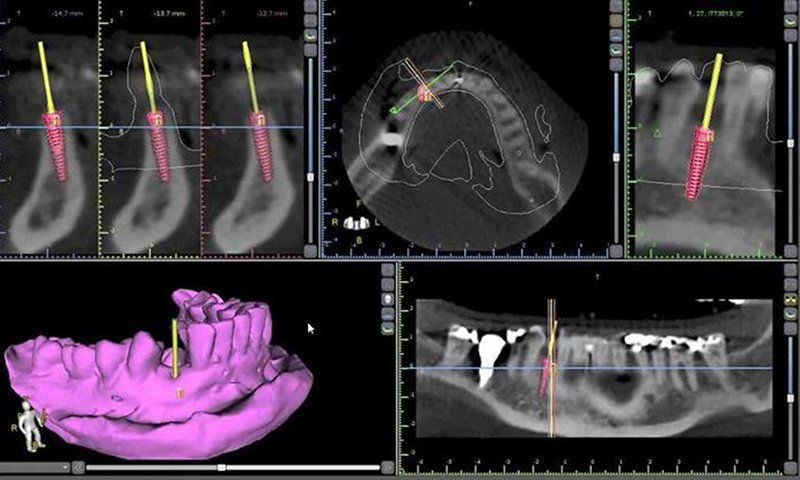

A Tomografia Computadorizada da Raio-X Mangabeiras possui a mais avançada técnica de aquisição volumétrica na odontologia e é uma importante ferramenta para o planejamento de procedimentos odontológicos, principalmente para o tratamentos com implantes, além de apresentar uma abordagem sistemática dos transtornos orais e das articulações da região da boca.